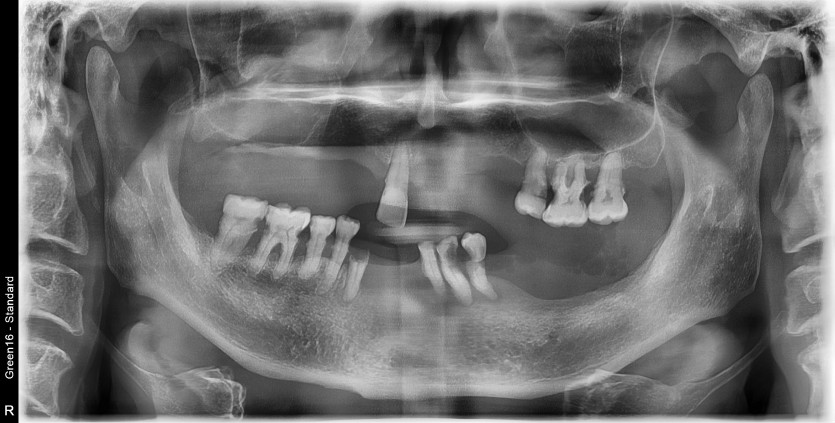

만 59세 전체 임플란트 증례

전체 임플란트 증례입니다.

18개의 임플란트로 완성하였습니다.